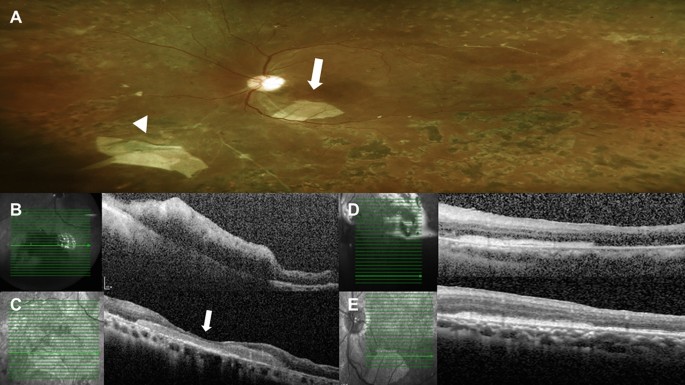

Postoperative color fundus photograph and serial optical coherence tomography (OCT) exams of case 7. (A) Color fundus photograph showed the one large retinal break securely covered by a human amniotic membrane (hAM) graft (arrow head). Also, there was one pice of hAM dislocated at the subretinal space within the vascular arcade intraoperatively (arrow). (B) Ten days after surgery, OCT scans over the location of retinal break showed the hAM graft covering the large break. (C) Six months later, follow-up OCT showed marked retina and glial tissue growing to cover the retina defect (arrow). And the graft remained stable without change in size. (D) Ten days after surgery, OCT scans of the dislocated subretinal hAM graft showed a sheet of hAM under the retina. (E) Six months later, the follow-up OCT revealed that there was no atrophy of the retina over the amniotic membrane. The retina structure remained intact and even more partial recovery of ellipsoid zone of the previous detached retina was observed.

For patients in the hAM group, eight cases had TRD with retinal breaks made during membrane delamination. Two cases had preoperative CTRRD. Table 2 shows the demographic data of the patients. Five eyes received silicone oil endotamponade, two eyes had 24% SF6 infusion, two eyes had 13% C3F8 infusion, and one eye had room air infusion. The mean follow-up duration was 6.78 months. Postoperatively, the retina was successfully reattached in all of the eyes. For five eyes with silicone oil tamponade, silicone oil was removed smoothly without recurrence after an average of 4.4 months. Fundus examinations, fundus photography, and serial OCT confirmed that the retinal breaks had been sealed by hAM grafts. Serial OCT revealed that all the hAM grafts stayed in place without dislocation. The graft size also seemed to be stationary without lysis. Moreover, from OCT, partial tissue regeneration was also observed over the retinal breaks (Fig. 1). In another patient (Fig. 2, case 7), the tissue regeneration effect was even more marked with the large retinal break all covered by regenerated glial and possible retinal tissue along the surface of the hAM graft. No postoperative major adverse event was found. An accident happened in one patient (Fig. 2D,E, case7); the break was too large, and the first hAM graft dislocated into the subretinal space during manipulation; thus, the second piece of the hAM was implanted, and the graft was positioned well into place under perfluorocarbon liquid. Postoperatively, the displaced subretinal hAM plug did not cause inflammation or retinal atrophy during serial postoperative OCT scans. Surprisingly, from the OCT, the partial recovery of the ellipsoid zone of the originally detached retina was observed.